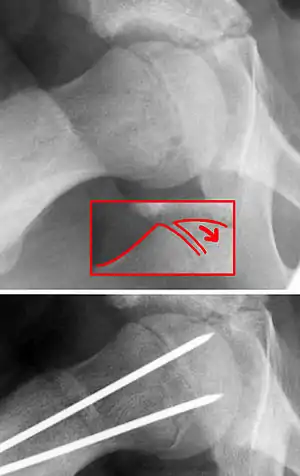

| X-ray showing a slipped capital femoral epiphysis, before and after surgical fixation. | |

The diagnosis requires x-rays of the pelvis, with anteriorposterior (AP) and frog-leg lateral views.[9] The appearance of the head of the femur in relation to the shaft likens that of a "melting ice cream cone", visible with Klein's line. The severity of the disease can be measured using the Southwick angle.

The disease can be treated with external in-situ pinning or open reduction and pinning. Consultation with an orthopaedic surgeon is necessary to repair this problem. Pinning the unaffected side prophylactically is not recommended for most patients, but may be appropriate if a second SCFE is very likely.[9]

Once SCFE is suspected, the patient should be non-weight bearing and remain on strict bed rest. In severe cases, after enough rest the patient may require physical therapy to regain strength and movement back to the leg. A SCFE is an orthopaedic emergency, as further slippage may result in occlusion of the blood supply and avascular necrosis (risk of 25 percent). Almost all cases require surgery, which usually involves the placement of one or two pins into the femoral head to prevent further slippage.[10] The recommended screw placement is in the center of the epiphysis and perpendicular to the physis.[11] Chances of a slippage occurring in the other hip are 20 percent within 18 months of diagnosis of the first slippage and consequently the opposite unaffected femur may also require pinning.

The risk of reducing this fracture includes the disruption of the blood supply to the bone. It has been shown in the past that attempts to correct the slippage by moving the head back into its correct position can cause the bone to die. Therefore the head of the femur is usually pinned 'as is'. A small incision is made in the outer side of the upper thigh and metal pins are placed through the femoral neck and into the head of the femur. A dressing covers the wound.